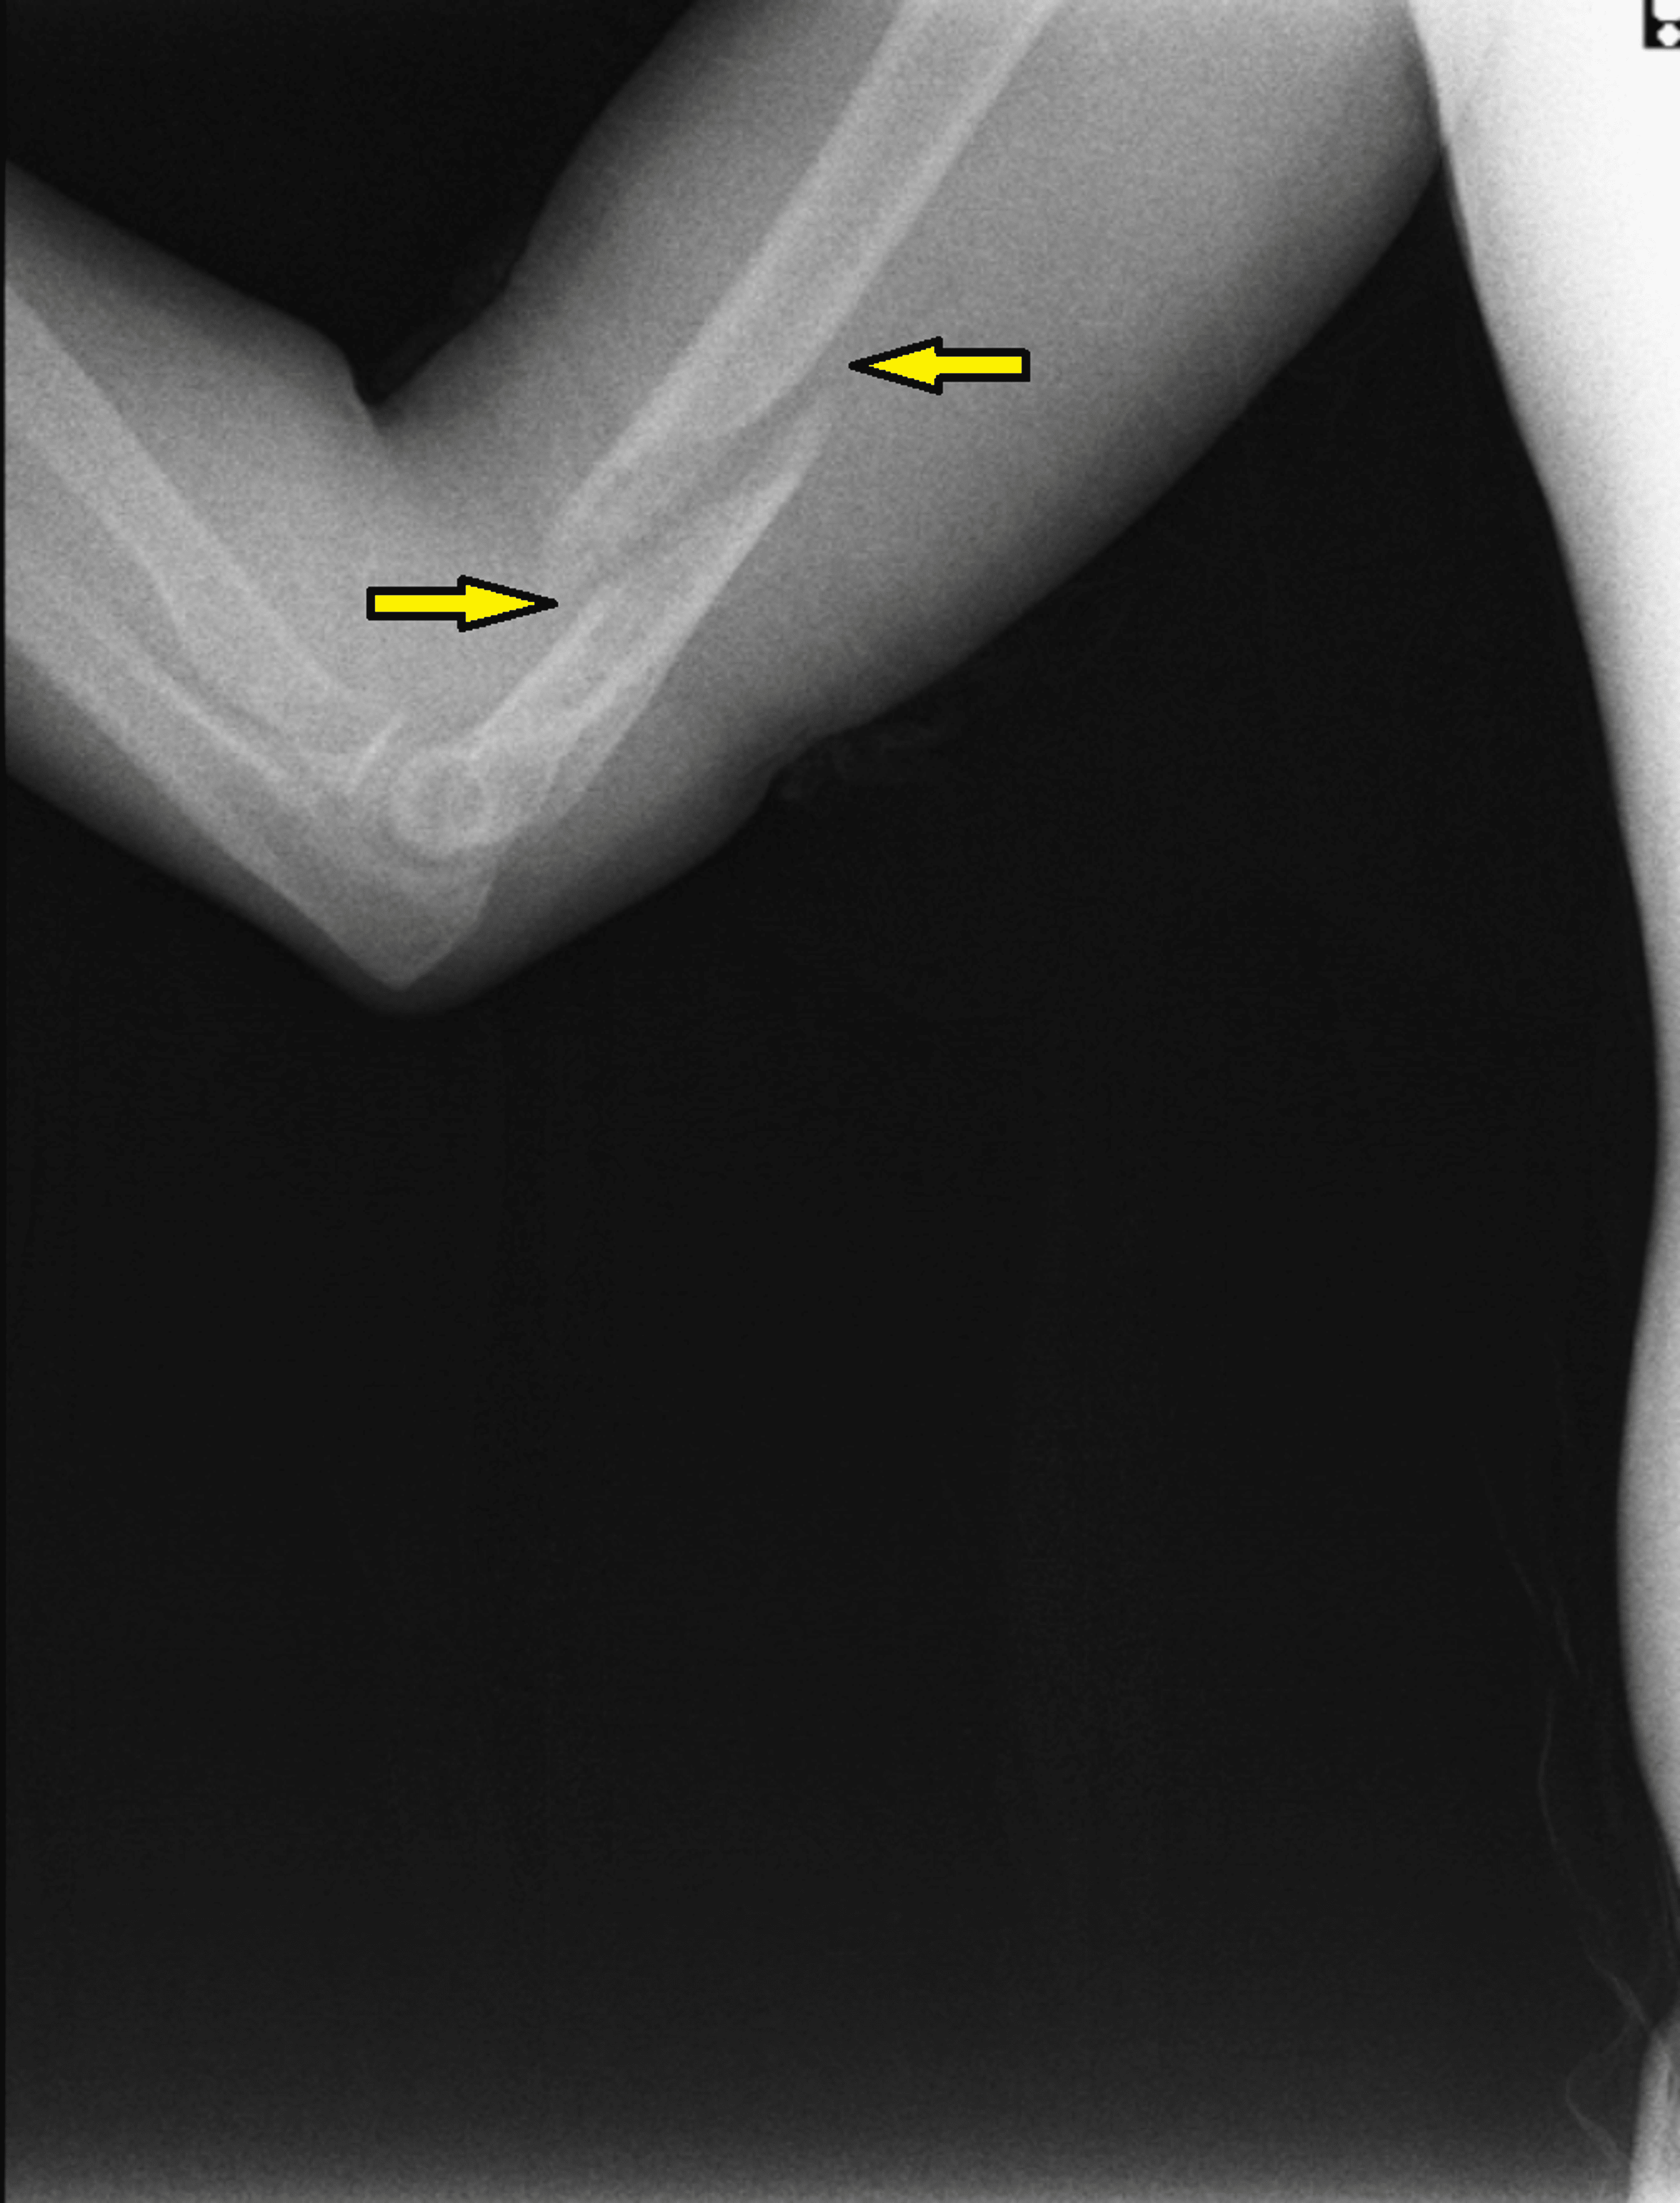

The different fracture patterns formed associated with arm wrestling

The different fracture patterns formed associated with arm wrestling Spiral Fracture Humerus Arm Wrestling This study aimed to elucidate the current. This study aimed to elucidate the current. Arm wrestling is an important cause of humerus shaft fracture. A spiral distal humeral shaft fracture is an unusual but significant injury that can result. The humerus fails due torsional and bending stresses. The most common injury associated with arm wrestling was spiral fractures of the. Spiral Fracture Humerus Arm Wrestling.